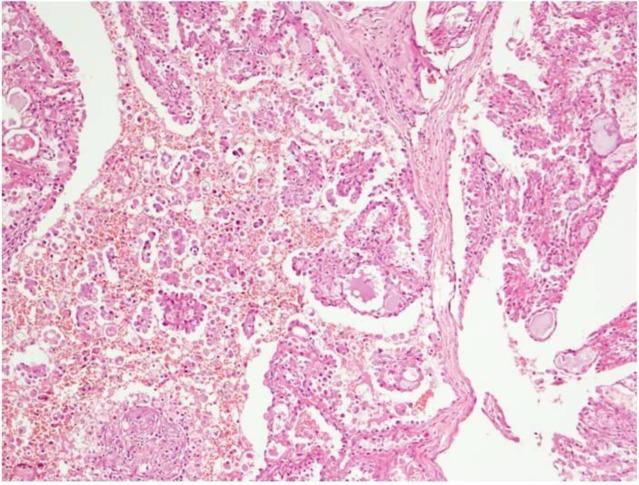

A 16-year-old male presented with recurrent painless swelling in the right preauricular region and with a history of surgical intervention at the same site in the past. His histopathology report was suggestive of pleomorphic adenoma. The swelling recurred after one year of excision and a superficial parotidectomy was performed. The detailed histopathological examination was suggestive of Polymorphous low grade adenocarcinoma. In view of close margins, the patient was given adjuvant radiotherapy. Thirty-three months post-surgery, he is alive and disease-free. We describe a rare case of PLGA of the parotid gland in a teenager with its clinical characteristics, histopathological features, and treatment.

The occurrence of PLGA in the parotid gland is rare with only a few cases reported in literature. The diagnosis of PLGA is challenging due to morphological diversity.